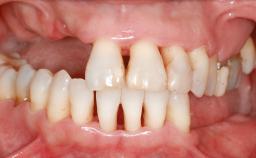

A 45-year-old woman with a completely edentulous maxilla was referred to evaluate the possibility of rehabilitation with an implant-supported prosthesis. This patient was healthy and a non-smoker. She had been wearing a maxillary complete denture opposing a natural mandibular dentition since her twenties. This situation had resulted in progressive resorption of the alveolar ridge, repeatedly creating a need for relining the denture. Twenty years later, despite multiple adaptations and the use of “glues” the denture was unstable and causing the patient psychological and functional discomfort.

Soft Tissue Anatomy Intact Defective

Bone Volume Horizontally and vertically sufficient Horizontally deficient Deficient vertically or deficient vertically AND horizontally

Soft Tissue Contour and Volume Significantly deficient